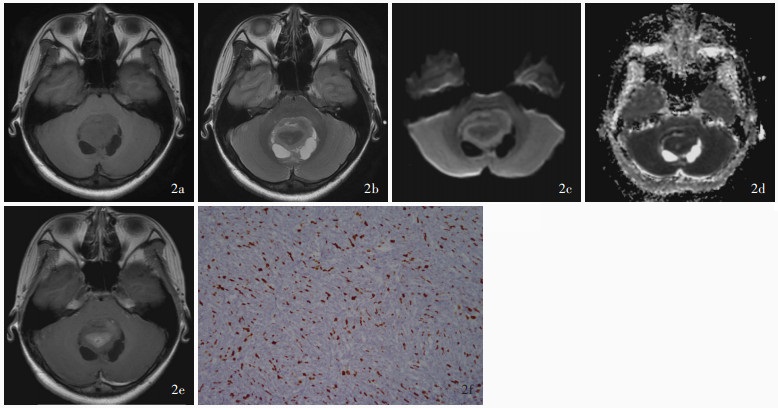

目的: 探讨儿童后颅窝常见肿瘤的影像学诊断与鉴别诊断方法,并按照先定位诊断再定性诊断的思路,基于DWI是否弥散受限提出儿童后颅窝常见肿瘤的诊断流程图。方法: 共纳入2021年1月至2024年1月在复旦大学附属华山医院予以手术切除的118例儿童后颅窝肿瘤患者,均行头部CT和MRI检查,并据此进行术前定位和定性诊断,分别以术中所见和术后病理学检查为诊断“金标准”,判断术前定位诊断和定性诊断的准确性;再基于DWI是否弥散受限提出儿童后颅窝常见肿瘤的诊断流程图。结果: 共118例后颅窝肿瘤患儿定位和定性诊断为第四脑室肿瘤计41例,包括髓母细胞瘤27例、毛细胞型星形细胞瘤7例、室管膜瘤5例、脉络丛乳头状瘤1例、形成菊形团的胶质神经元肿瘤1例;脑干肿瘤38例,包括弥漫性中线胶质瘤,H3 K27变异型24例、毛细胞型星形细胞瘤5例、海绵状血管瘤3例、儿童型弥漫性高级别胶质瘤(倾向弥漫性中线胶质瘤,H3野生型)2例、节细胞胶质瘤2例、非典型性畸胎样/横纹肌样肿瘤1例、儿童型弥漫性低级别胶质瘤1例;脑桥小脑角肿瘤计9例,包括毛细胞型星形细胞瘤3例、胆脂瘤2例、髓母细胞瘤1例、弥漫性中线胶质瘤,H3 K27变异型1例、毛细胞黏液型星形细胞瘤1例、尤文肉瘤1例;小脑肿瘤计30例,包括毛细胞型星形细胞瘤15例、髓母细胞瘤7例、海绵状血管瘤2例、室管膜瘤1例、儿童型弥漫性低级别胶质瘤1例、儿童型弥漫性高级别胶质瘤(倾向弥漫性中线胶质瘤,H3野生型)1例、胚胎发育不良性神经上皮肿瘤1例、错构瘤1例和肾外横纹肌样瘤小脑转移瘤1例。定位诊断,术前CT的定位诊断准确率为93.22%(110/118),MRI的定位诊断准确率达100%(118/118)。定性诊断,74例(62.71%)患儿定性诊断准确,23例(19.49%)诊断笼统,21例(17.80%)诊断错误。儿童后颅窝肿瘤的影像学鉴别诊断集中于髓母细胞瘤、毛细胞型星形细胞瘤、室管膜瘤、弥漫性中线胶质瘤,H3 K27变异型。位于脑干外的髓母细胞瘤、毛细胞型星形细胞瘤和室管膜瘤的DWI弥散受限发生率分别为100%(35/35)、4%(1/25)和5/6,3种肿瘤之间差异有统计学意义(Z=-5.601,P=0.000);位于脑干的弥漫性中线胶质瘤,H3 K27变异型和毛细胞型星形细胞瘤的DWI弥散受限发生率为79.17%(19/24)和1/5,两种肿瘤之间差异亦有统计学意义(Fisher确切概率法:P=0.038)。结论: 儿童后颅窝肿瘤早期诊断较为困难,DWI是鉴别诊断的重要依据,基于DWI是否弥散受限提出的儿童后颅窝常见肿瘤诊断流程图有望提高术前诊断的准确性。

Objective: To investigate the imaging diagnosis and differential diagnosis methods for common tumors in the posterior fossa of children, and to propose a flow chart for the diagnosis of common tumors in the posterior fossa of children based on the limited diffusion of DWI according to the idea of localization diagnosis followed by qualitative diagnosis. Methods: A total of 118 pediatric patients with posterior fossa tumors who underwent surgical resection in Huashan Hospital, Fudan University from January 2021 to January 2024 were enrolled, and all of them underwent head CT and MRI examinations, and preoperative localization diagnosis and qualitative diagnosis were carried out accordingly. Then, based on whether DWI was diffusion limited, a flow chart for the diagnosis of common tumors in the posterior fossa of children was proposed. Results: A total of 118 children with posterior fossa tumors were localization and qualitatively diagnosed, including 41 cases of fourth ventricular tumors, including medulloblastoma (27 cases), pilocytic astrocytoma (7 cases), ependymoma (5 cases), choroid plexus papilloma (one case), and rosette-forming glioneuronal tumor (RGNT, one case). There were 38 cases of brainstem tumors, including 24 cases of diffuse midline glioma, H3 K27-altered, 5 cases of pilocytic astrocytoma, 3 cases of cavernous hemangioma, 2 cases of pediatric-type diffuse high-grade glioma (prone to diffuse midline glioma, H3 wild type), 2 cases of ganglio glioma, one case of atypical teratoid/rhabdoid tumor (AT/RT), and one case of pediatric-type diffuse low-grade glioma. There were 9 cases of cerebellopontine angle (CPA) tumors, including 3 cases of pilocytic astrocytoma, 2 cases of cholesteatoma, one case of medulloblastoma, one case of diffuse midline glioma, H3 K27-altered, one case of pilomyxoid astrocytoma, and one case of Ewing sarcoma. There were 30 cases of cerebellar tumors, including 15 cases of pilocytic astrocytoma, 7 cases of medulloblastoma, 2 cases of cavernous hemangioma, one case of ependymoma, one case of pediatric-type diffuse low- grade glioma, one case of pediatric-type diffuse high- grade glioma (prone to diffuse midline glioma, H3 wild type), one case of dysembryoplastic neuroepithelial tumor (DNT), one case of hamartoma, and one case of extrarenal rhabdomyomatoid tumor cerebellar metastases. Localization diagnosis, the accuracy of preoperative CT was 93.22% (110/118), while the accuracy of preoperative MRI was 100% (118/118). Qualitative diagnosis, 74 cases (62.71%) had accurate qualitative diagnosis, 23 cases (19.49%) had general diagnosis, and 21 cases (17.80%) had wrong diagnosis. The imaging differential diagnosis of posterior fossa tumors in children focuses on medulloblastoma, pilocytic astrocytoma, ependymoma, and diffuse midline glioma, H3 K27-altered. The incidence of limited diffusion of DWI in medulloblastoma, pilocytic astrocytoma and ependymoma outside the brainstem was 100% (35/35), 4% (1/25) and 5/6, and the difference among the three tumors was statistically significant (Z =-5.601, P = 0.000). The incidence of limited diffusion of DWI in diffuse midline glioma, H3 K27-altered and pilocytic astrocytoma in the brainstem was 79.17% (19/24) and 1/5, and the difference between the two tumors was also statistically significant (Fisher's exact possibility: P = 0.038). Conclusions: The early diagnosis of posterior fossa tumors in children is difficult, and DWI is an important basis for differential diagnosis.